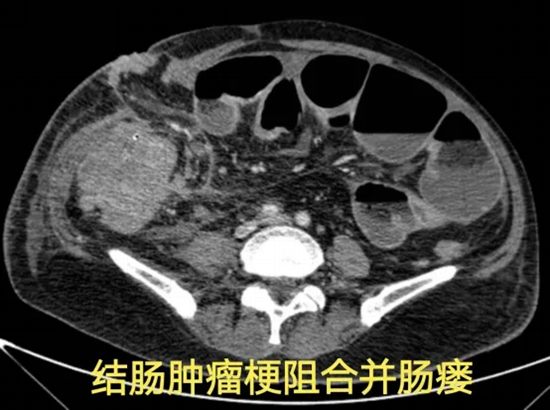

病情简述:69岁男性,ESD术后结肠穿孔,引发腹膜后感染。

诊疗破局:急诊腹腔镜探查发现瘘口。术中评估感染尚局限,团队果断选择“直肠瘘修补+冲洗引流”的保守手术方案,成功为患者保住了肠道,避免了结肠造口。

技术体现:在急重症处理中,贯彻快速康复理念,以最小创伤解决大问题,是医者不懈的追求。